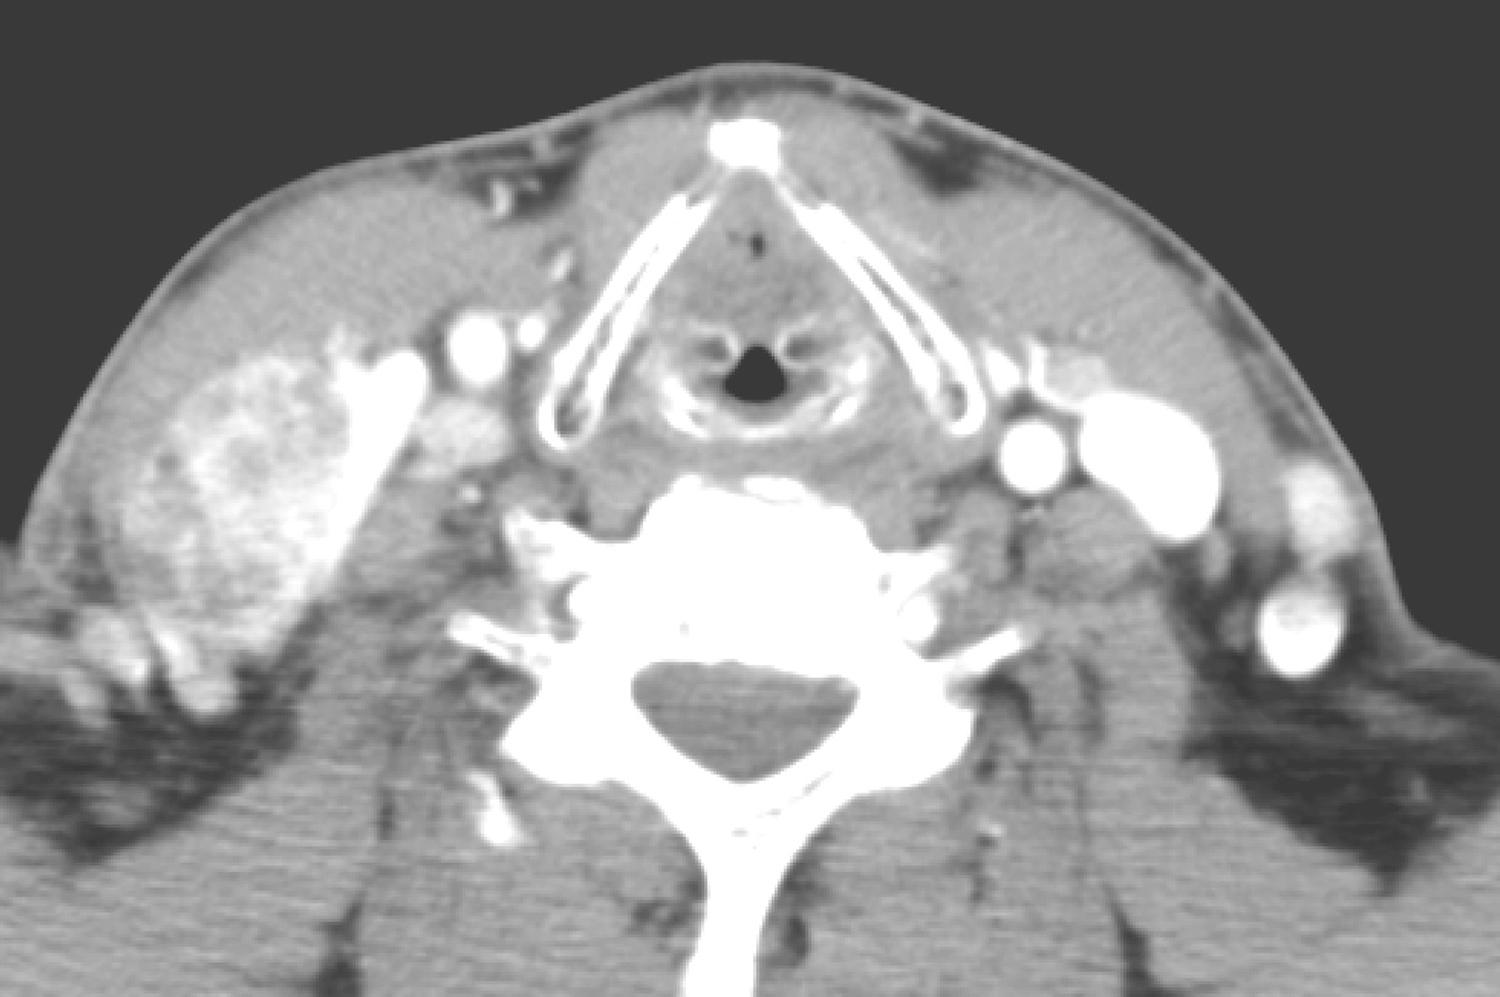

右颈Ⅱ、Ⅲ、Ⅳ区及左颈Ⅳ区、右食管气管沟、纵隔1、2R、4R区多发肿大淋巴结,较大者约3.3cm×2.1cm,不均匀强化(图2、图3)。

图2 颈部增强CT示右侧颈部肿大淋巴结

图3 胸部增强CT示纵隔多发肿大淋巴结